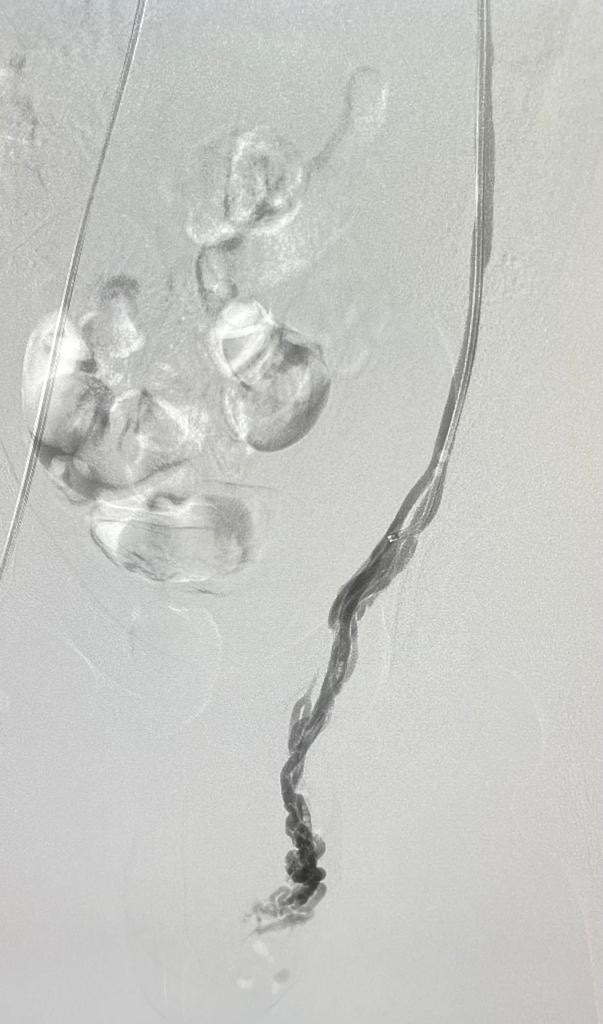

Varicocoeles?

A varicocele is an enlargement of the veins within the loose bag of skin that holds your testicles (scrotum). It’s similar to a varicose vein you might see on your leg. Varicoceles are a common cause of low sperm production and decreased sperm quality, which can cause infertility.